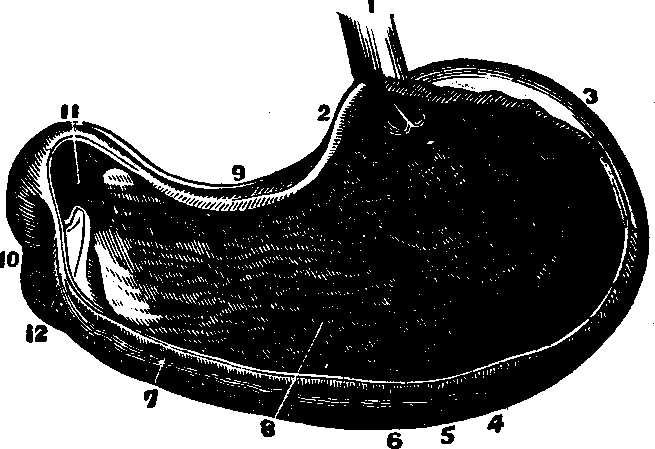

Fig. 28. A representation of the

interior of the stomach. 1. The esophagus. 2. Cardiac orifice

opening into the stomach. 6. The middle or muscular coat. 7.

The interior or mucous coat. 10. The beginning of the duodenum.

11. The pyloric orifice.

The Stomach is a musculo-membranous, conoidal sac, communicating

with the esophagus by means of the cardiac orifice (see Fig. 28). It is

situated obliquely with reference to the body, its base lying at the left

side, while the apex is directed toward the right side. The stomach is

between the liver and spleen, subjacent to the diaphragm, and communicates

with the intestinal canal by the pyloric orifice. It has three coats. The

peritoneal, or external coat is composed of compact, cellular tissue, woven

into a thin, serous membrane, and assists in keeping the stomach in place.

The middle coat is formed of three layers of muscular fibers: in the first,

the fibres run [pg

40]longitudinally; in the second, in a circular direction; and in

the third, they are placed obliquely to the others. The interior, or mucous

coat, lines this organ. The stomach has a soft, spongy appearance, and,

when not distended, lies in folds. During life, it is ordinarily of a

pinkish color. It is provided with numerous small glands, which secrete the

gastric fluid necessary for the digestion of food. The lining membrane,

when divested of mucus, has a wrinkled appearance. The arteries, veins, and

lymphatics, of the stomach are numerous.